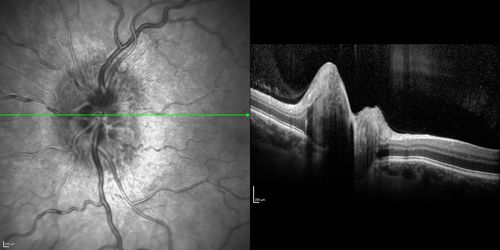

Optic Nerve (Disc) Drusen - Spectral Domain Optical Coherence Tomography Line Scan

34 Year Old woman no headaches normal vision

Optic Nerve Drusen - Buried and Not Calcified - Optical Coherence Tomography